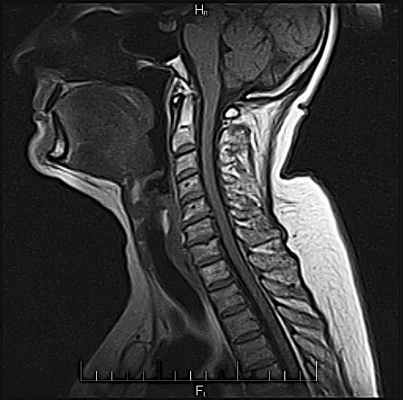

МРТ шеи. МРТ шейного отдела позвоночника

МРТ шеи (шейного отдела позвоночника) – исследование, которое показывает состояние одной из наиболее важной части тела.

Шея вмещает в себя много органов. На МРТ шеи видны позвоночник, горло, гортань, трахея, щитовидная и паращитовидная железа, кровеносные сосуды и др. Шея – это анатомическое наиболее подвижна часть тела. Поэтому наиболее частым объектом исследования при МРТ шеи является шейный отдел позвоночника. МРТ исследование показывает состояние не только шейных позвонков, но и дисков. Как правило проводится измерение сечения позвоночного канала на уровне выпячивания дисков, что есть крайне важной информацией для принятия решения о лечении. Следует отметить, что эти показатели важны при МРТ исследовании любого отдела позвоночника.

На МРТ шеи виден спинной мозг. Современные аппараты позволяют уточнить состояние тканей спинного мозга, вовремя выявить т.н. миелопатию (изменение структуры спинного мозга).

Важной особенностью шеи есть то, что через нее проходят сосуды, которые питают головной мозг. Это сонные и позвоночные артерии. Сосуды шеи – один из объектов исследования при МРТ шеи. Исследование сосудов шеи, как правило проводится вместе с сосудами головы (МРТ головы и шеи). По своей сути эти сосуды являются одним целым и предусматривает диагностику сосудов головы и шеи одним пакетом.

Патология шейного отдела позвоночника может привести к нарушению кровоснабжения головного мозга и к развитию неврологической патологии. Поэтому МРТ шеи – это процедура не только для ортопедов и нейрохирургов, но и для неврологов. Врач невропатолог привязывает данные МРТ шейного отдела позвоночника к клиническим признакам и, таким образом, может установить т.н. топический диагноз (сопоставить уровень поражения нервной системы с уровнем изменений в позвоночнике).

Изменения в шейном отделе позвоночника может проявляться болью, которая может распространяться в надплечья и в руки. Также патология шейных дисков или спондилез позвонков шеи может причинять боль в грудной клетке сзади. Это отраженные или проекционные боли. Если немеют руки, в первую очередь необходимо думать о проблемах с шейным отделом позвоночника и проводить МРТ шеи.

Боли в шее могут быть следствием патологии не только позвоночника, но и мягких тканей. Поэтому МРТ мягких тканей шеи – важная составляющая обследования. Оцениваются околопозвоночные мышцы и передняя группа мышц. Просматривая МРТ шеи, доктор уточняет строение верхних дыхательных путей, их проходимость, соседние ткани.